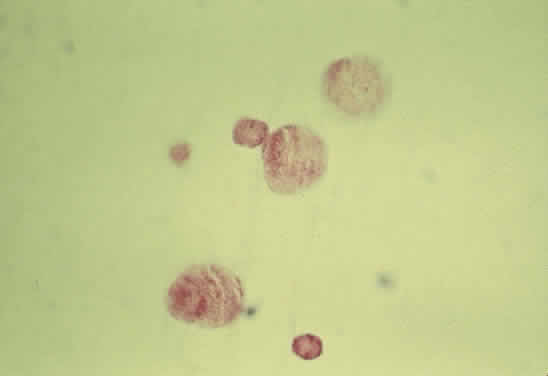

Fig. 53. Trypsin digest of the retinal capillary circulation demonstrating microaneurysm

formation. (Courtesy of Ralph C. Eagle Jr, MD, Philadelphia, PA) Fig. 53. Trypsin digest of the retinal capillary circulation demonstrating microaneurysm

formation. (Courtesy of Ralph C. Eagle Jr, MD, Philadelphia, PA)